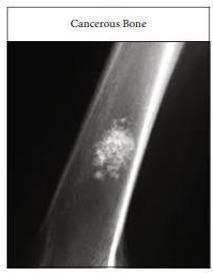

enlargesgraduallyuntilitreachesneighboringpartsofthe body. Bone tissue suffers severe damage as well as bones become weaker through this specific action. The statistics in2018showedthat3,500Americanswerediagnosedwith bone cancer and thediseaseclaimed 47% oftheir lives. Xrayimagingstandsasavitaltoolfordetectingmalignancies becauseitserves as one of several diagnostic tests used in bone cancer detection. The assimilation rate of malignant bone tissue differs from normal tissue which produces irregularandbrokenX-rayimages(Oishilaetal.,2018)[2].

The evaluation of bone cancer development relies on stage and grade assessment while the speed of tumor expansion including its destructive traits towards bone tissue (geographic bone destruction) serves as a vital diagnostic element. Medical diagnosis of cancers often requires extensive time from physicians and it remains prone to misdiagnosis. The survival rate for cancer patients becomes higher when cancer is detected at an early stage. The proposed system uses Support Vector Machines together with image processing methods to identify and classify bone tumors. Various studies attempted to generate systems which aid medical workers in their duties through automated diagnosis solutionscoupledwithtechniquestodecreasediagnostic time and reduce errors. Research literature demonstrates how existing systems employ the combination of Support Vector Machines with digital image processing methods involving preprocessing and edge detection and feature extraction to achieve these results(Chenetal.,2007)[3].